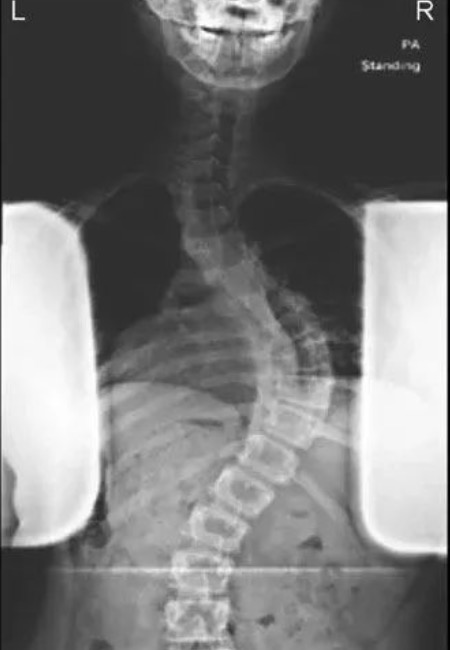

脊椎侧弯对健康的影响,除了体态外观上的问题外,多半会引起长期的腰背酸痛,另外脊椎关节在长期受力不均之下,可能发生退行性关节炎;如果侧弯持续增大,可影响心肺功能;非常严重的畸形也可能会压迫神经根和脊髓,引起瘫痪。对于脊柱侧弯,早期发现非常重要,家长有助于早期发现,那么,如何能早期发现孩子患有脊柱侧弯呢.....

脊柱侧弯学名脊柱侧凸,孩子患了脊柱侧凸,家长都比较着急,四处寻医,奔波折腾,心里没有底,小编组织了有关脊柱侧弯的一些问题,希望患者和家长正确认识,回归理性! 本期主要内容:认识脊柱侧凸,脊柱侧凸的病因、筛查常见的问题。 下期内容:脊柱侧凸研究进展、治疗方案、支具方面的问题。 文章来源: 国际.....

特发性脊柱侧凸患者以青少年、女性多见,在整个的治疗过程中将要接受多次X线检查。已有研究报道了脊柱侧凸患者乳腺癌1和甲状腺癌2的发生率明显增加,研究者将其归咎于影像学检查带来的放射暴露。 避免不必要的影像学检查是减少放射暴露的关键。对日常工作中不接触辐射性工作的人来说,每年正常的天然辐射(主要是因为空.....